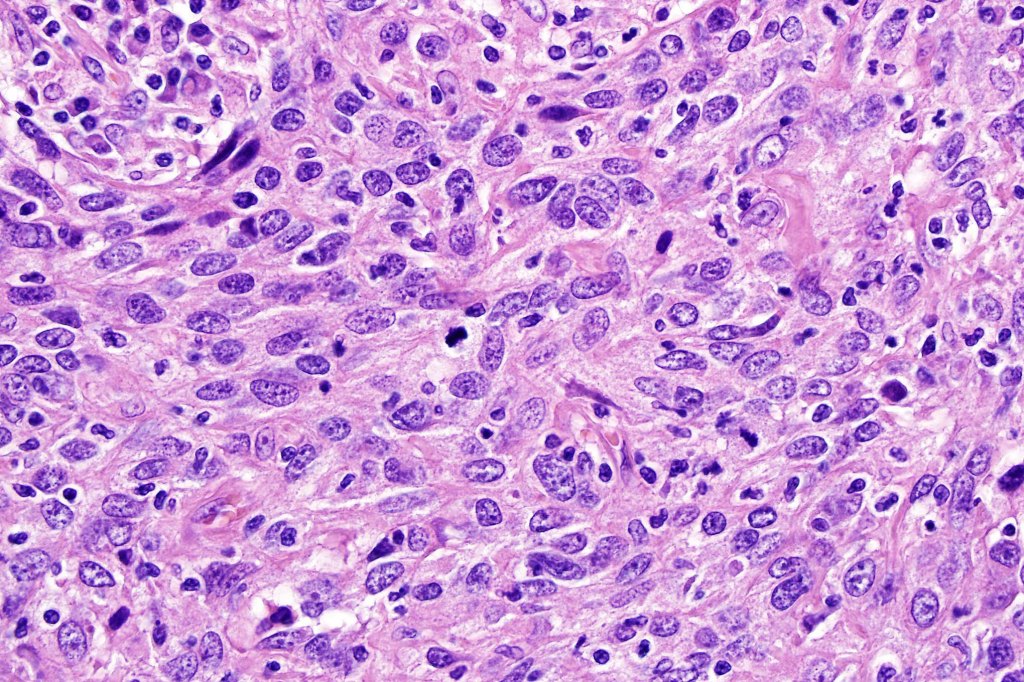

•Syncytial epithelial component in nests, cords or sheets surrounded by an intense lymphoplasmacytic infiltrate

•Epithelial cells are large with abundant cytoplasm and vesicular nuclei with conspicuous nucleoli

•Marked mitotic activity, variable pleomorphism